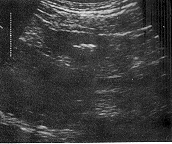

按照小肠肿瘤的超声图像分型〔7〕,本组21例转移性小肠肿瘤中19例均属壁厚型。肿瘤大体形态和长、短轴切面为受累肠壁增厚分别显示为假肾和靶环征(图1.2)。厚度范围0.8~2.0cm,长度范围3.0~7.0cm;2例长度>10cm分别为鼻咽部恶性淋巴瘤和白血病远端小肠侵犯,沿肠壁长轴浸润呈均匀低回声区(图3)。2例属腔外肿块型。11例为卵巢癌腹膜种植性转移连同小肠襻与壁层腹膜之间Φ3.0cm中等强回声型肿块并有多量腹水(图4)。另1例为睾丸精原细胞瘤小肠转移,相当于远端小肠与膀胱之间见Φ6.0cm中等回声实性肿块伴边缘肠腔强回声及膀胱内游离气体,提示:小肠外生型肿瘤侵犯膀胱并有内瘘形成,X线气钡双重对比造影后患者排出白色钡剂尿液(图5,6)。

长轴呈典型“假肾”征 短轴切面,大致呈“靶环”征

图1 壁厚型,转移性小肠肿瘤 图2 转移性小肠肿瘤